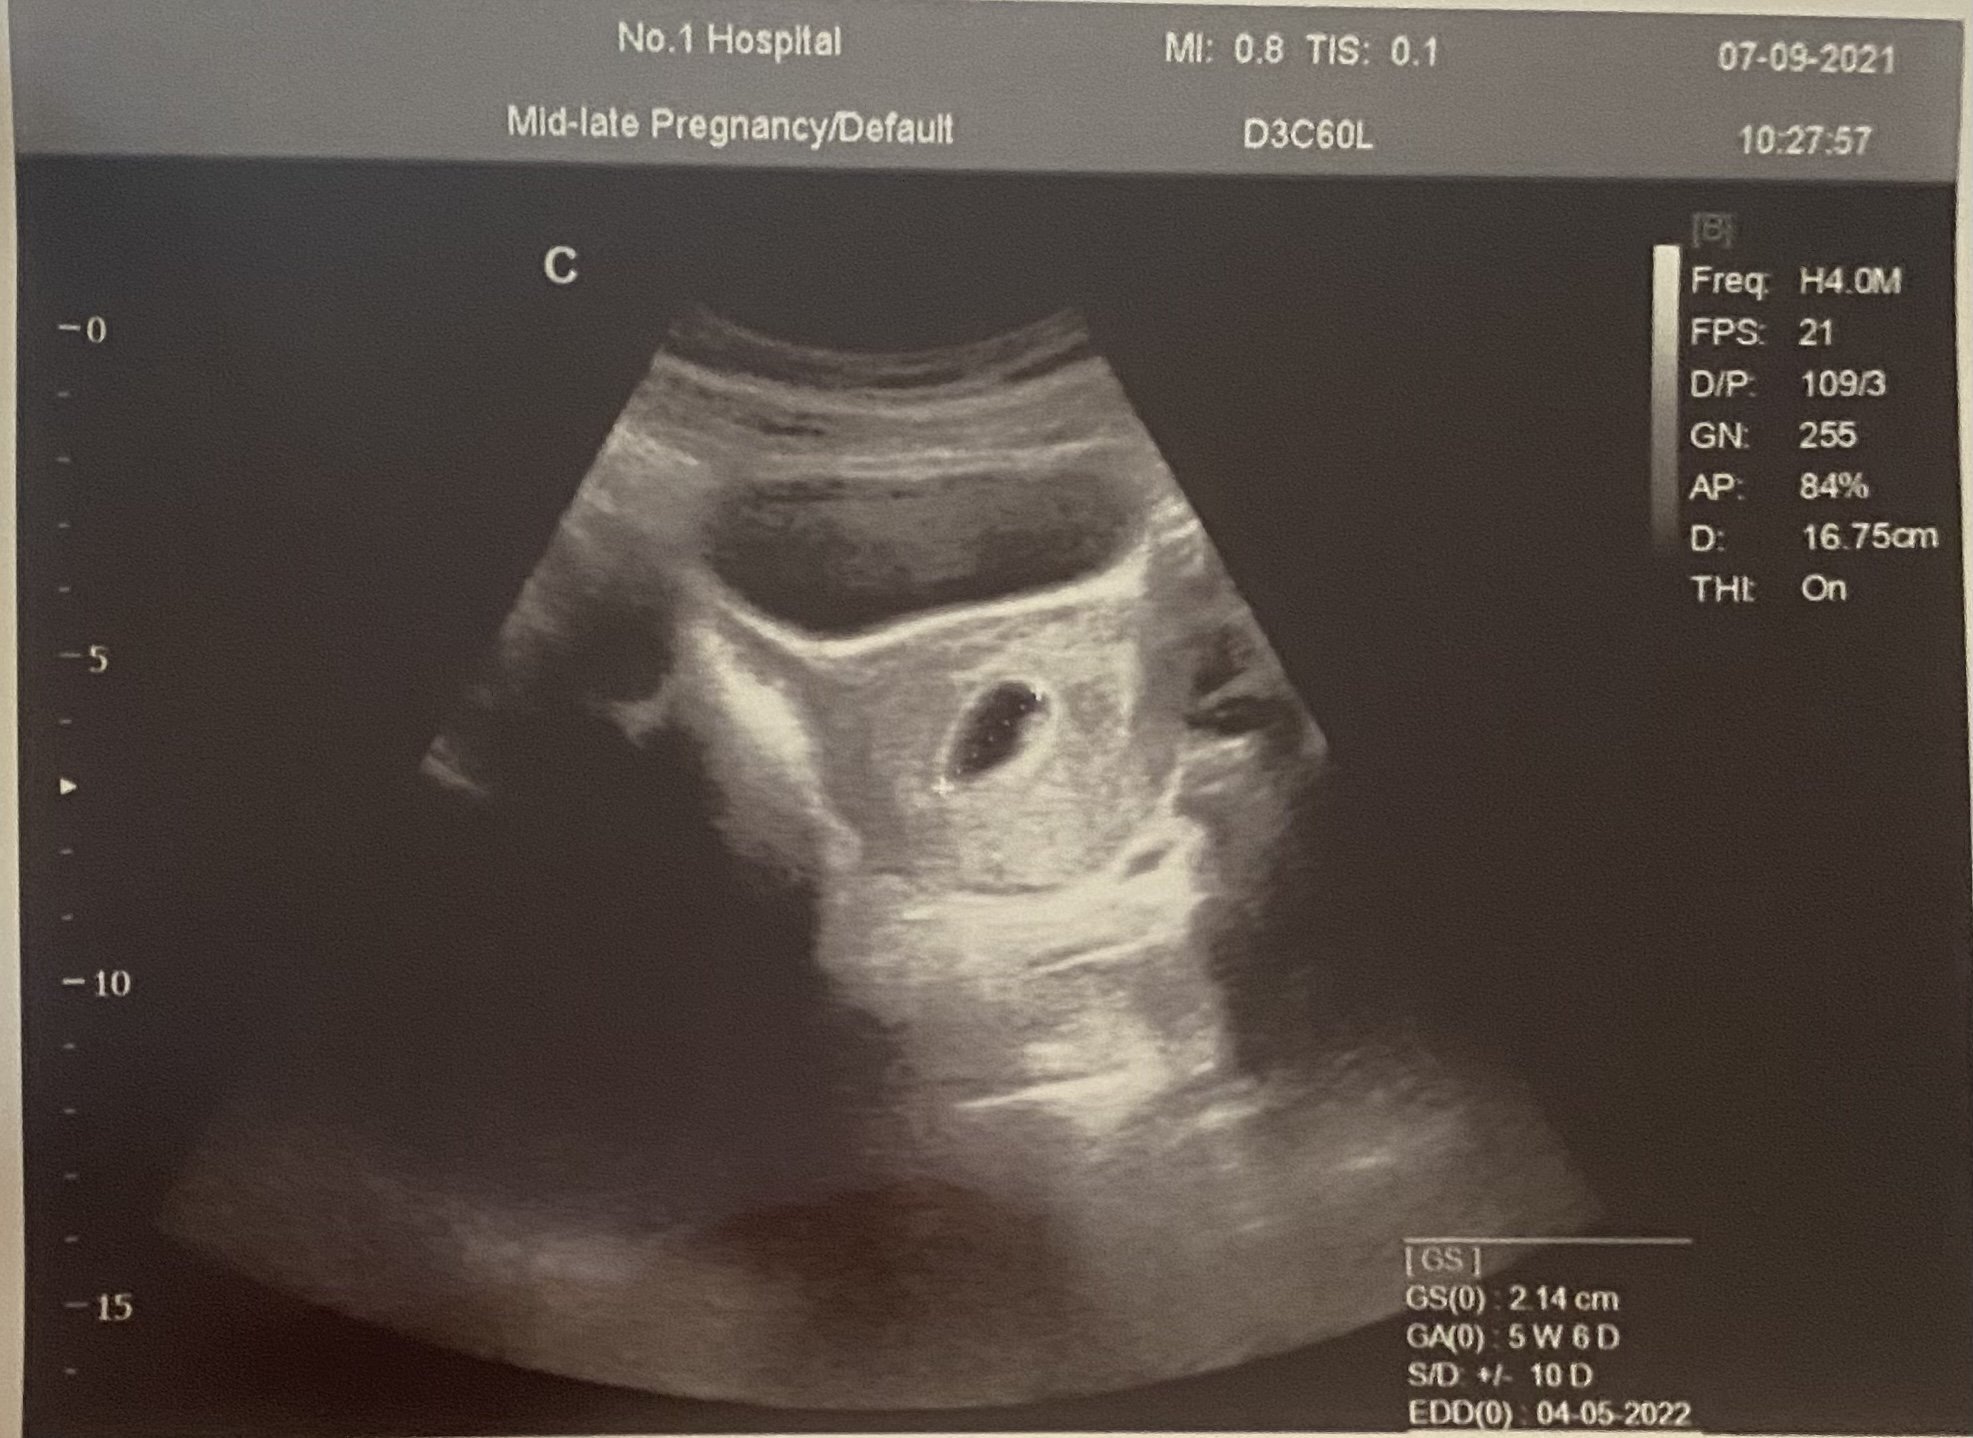

Здравейте момичета. Бременна съм в 5-та г.с и 6 дни. Днес бях на преглед и гинеколожката ми каза, че бебето е прекалено малко за седмиците си и страшно много се разтревожих. Много ще се радвам ако споделите размерите на вашите бебчета.

5+6 сте по последна менструация, а докторът колко измери? Възможно е да сте била с по-късна овулация и затова да е по-малко, а и в началото става въпрос за милиметри и може да не е измерено точно.

Ани, размери в тези ранни седмици не могат да се сравняват. Изчакай две, три седмици преди да се тревожиш. Нека се чуе сърчице. Може да си имала късна овулация просто.